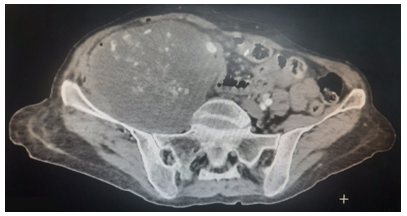

A thoracic-abdomen-pelvic CT scan revealed a process occupying the entire cecum and extending upwards to the ascending colon, with significant densification of the peri-lesional mesenteric fat and multiple satellite adenopathies.

An MRI scan showed an abscess of the right iliac psoas measuring 83 x 84 cm and extending over a height of 105 mm (Figure 1).

The patient underwent right hemicolectomy by laparotomy for a locally advanced tumour perforated posteriorly at the level of the right psoas muscle, with immediate restoration of continuity, abundant peritoneal cleansing and lamellar drainage. The post-operative course was straightforward. The histological study classified the adenocarcinoma with poorly cohesive cells as pT3N0M0(UICC Stage II) and the patient did not receive any adjuvant treatment despite our insistence on the perforated nature of the mass and the risk of peritoneal spread. Two years later, the patient presented with a recurrence in the form of a huge right psoas mass containing fine calcifications (Figure 2). It was only then that the oncologists decided to start her on chemotherapy. The patient died a few months later.